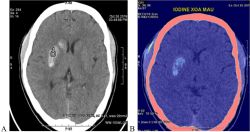

Khối u não

- Có nhiều loại, trong số đó có những khối u ác tính và những khối u não lành tính.

- Một khối u não ác tính bắt nguồn từ não được gọi là u (ung thư) não nguyên phát.

- Một khối u não do một ung thư từ nơi khác của cơ thể di chuyển vào não được gọi là ung thư não thứ phát, hay còn gọi là di căn não.